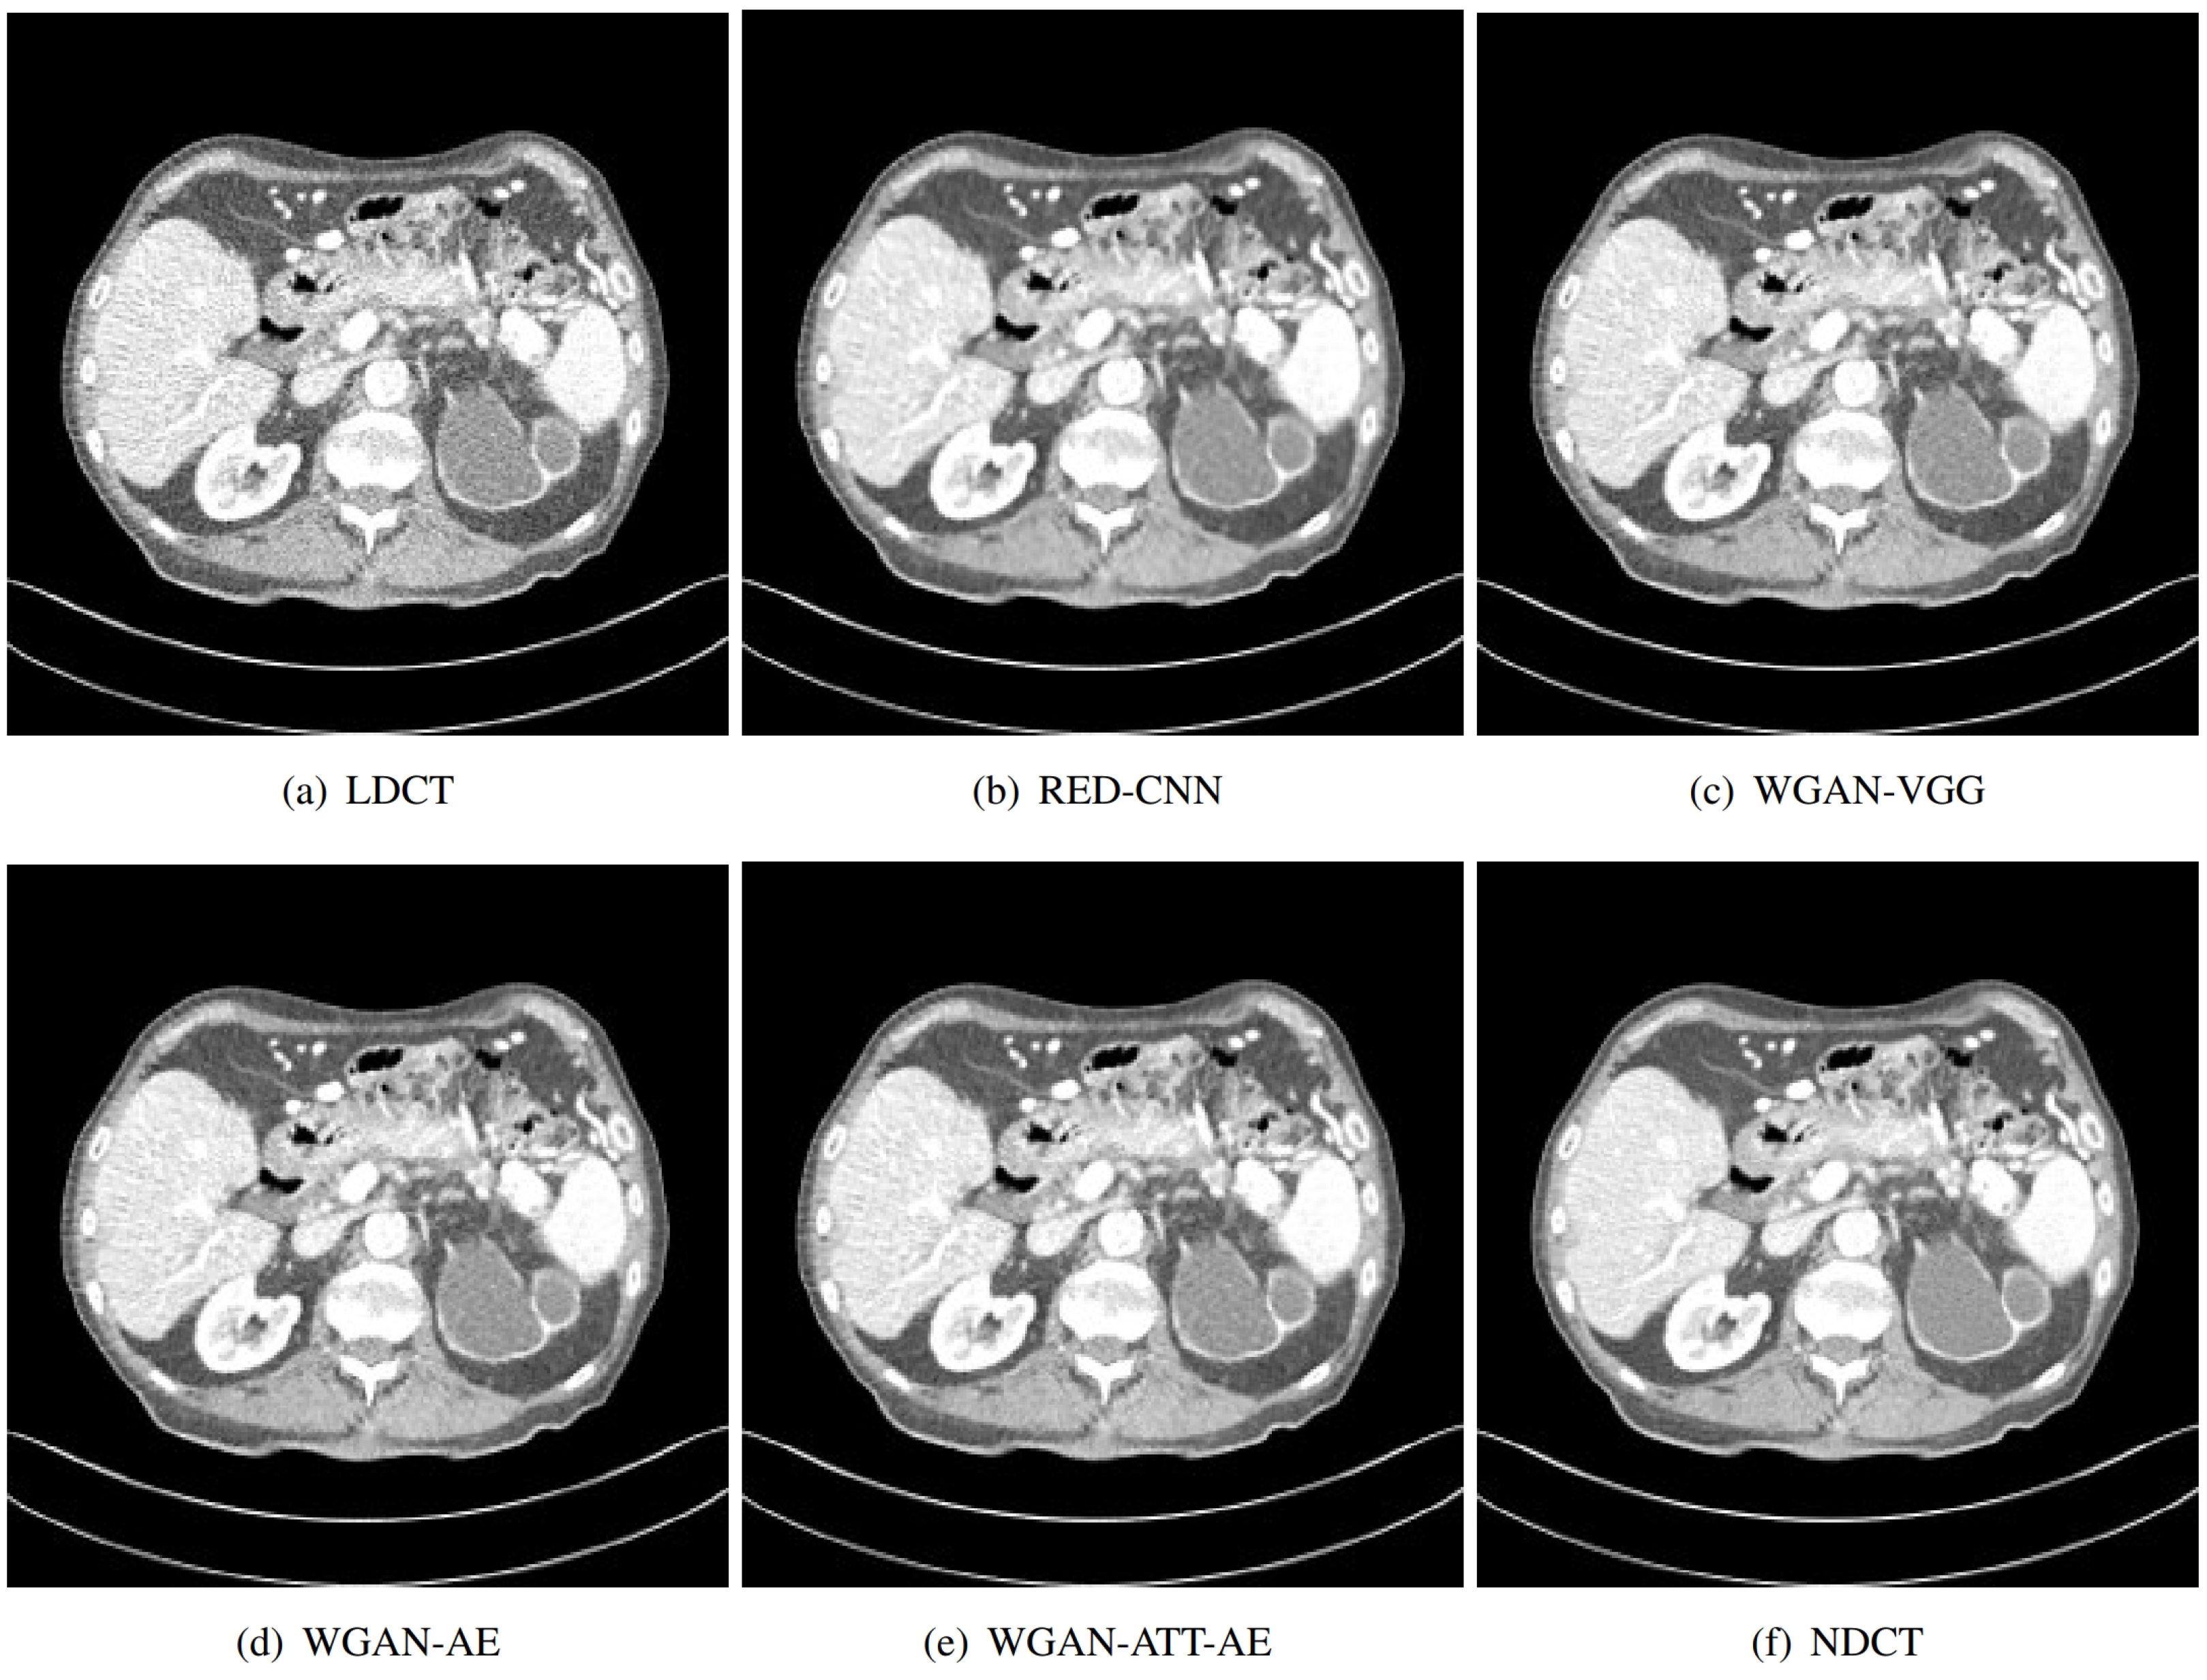

Figure 11.

Comparison of local magnification of low-dose CT image denoising results using different methods.

Figure 11 shows an enlarged view of a specific region from the same set of abdominal CT scans used in the first image, focusing on the details provided by each method. The region in the LDCT image shows a significant amount of grainy noise, which obscures finer details and makes it difficult to interpret anatomical structures accurately. While RED-CNN reduces some noise, it still leaves a considerable amount of granularity, and some details are smoothed out. The WGAN-VGG method reduces noise effectively but introduces a slight blurring, which could affect the clarity of fine structures. This method provides a clearer image than the previous methods, with better detail retention and reduced noise. Our proposed method shows the best performance, significantly reducing noise while preserving fine details and textures, closely matching the quality of the NDCT. As the ground truth, the NDCT image presents the highest quality with minimal noise and clear anatomical details.

We conducted qualitative and quantitative analysis, and we compared the effects of the proposed methods (WGAN-AE, WGAN-ATT-AE) and the baseline method (WGAN-VGG) on locally enlarged images. The results show that the important anatomical structure and detailed information in the image can be effectively maintained while reducing noise, while the baseline method shows a greater degree of information loss. This finding further validates the superiority of the proposed method in maintaining image quality and highlights its potential application value in clinical diagnosis. The proposed method can better maintain detail information and structural integrity in locally enlarged images, and presents a clearer and more accurate enlargement effect compared with baseline methods. This finding highlights the superiority of the proposed method in image enhancement and provides more reliable support for clinical diagnosis, providing a further comparison of the performance of different methods in preserving image details and structure.

In conclusion, the interpretation of the local magnification results in CT images in the comparative experiments provides a comprehensive evaluation of the performance of the proposed method in image enhancement tasks and highlights its superiority in maintaining image details and structural integrity. These findings not only help to verify the effectiveness of the proposed method, but also provide an important reference for its application in clinical practice and provide useful inspiration for future research and technology development.